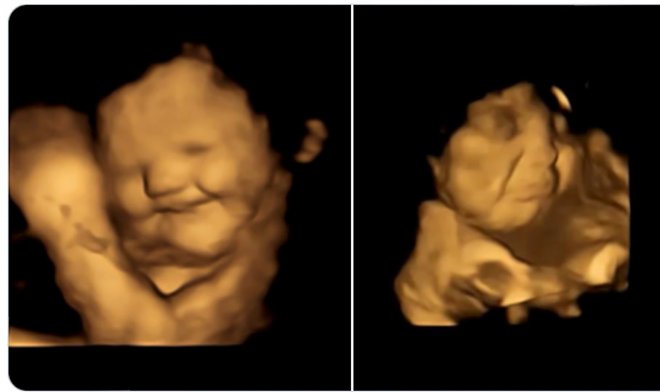

Реакция плода на вкус капусты кейл

Женщинам давали пилюли с порошком капусты кейл и морковки. Первый отличается горьким вкусом, второй воспринимается как сладкий, хотя там нет сахара. В результате сканер зафиксировал отчетливую реакцию плода – их личики морщились или улыбались в ответ на горький или сладкий вкус, соответственно. Данные были проверены на контрольной группе, которая не получала никаких особенных вкусовых веществ.